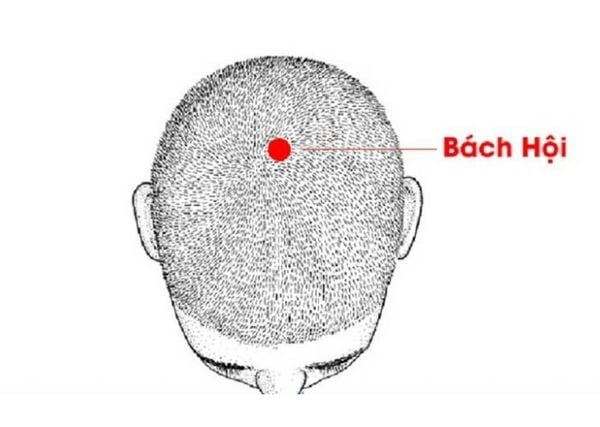

2. Huyệt Bách Hội: Day bấm huyệt Bách Hội cho người hay mệt mỏi, choáng váng, đầu óc nặng hoặc chóng mặt kéo dài.

– Vị trí: Nằm ở điểm giữa đỉnh đầu; có thể xác định bằng cách nối một đường tưởng tượng từ đỉnh tai trái sang đỉnh tai phải, điểm giữa chính là huyệt Bách Hội.

– Tác dụng: Giúp giảm cảm giác nặng đầu, hỗ trợ cải thiện sự tỉnh táo và giảm choáng váng.

– Cách thực hiện: Dùng đầu ngón tay giữa day tròn nhẹ hoặc ấn giữ trong 1–2 phút; có thể thực hiện vào buổi sáng sau khi thức dậy hoặc khi cảm thấy mệt mỏi trong ngày.

Day bấm huyệt Bách Hội cho người hay mệt mỏi, choáng váng, đầu óc nặng hoặc chóng mặt kéo dài.